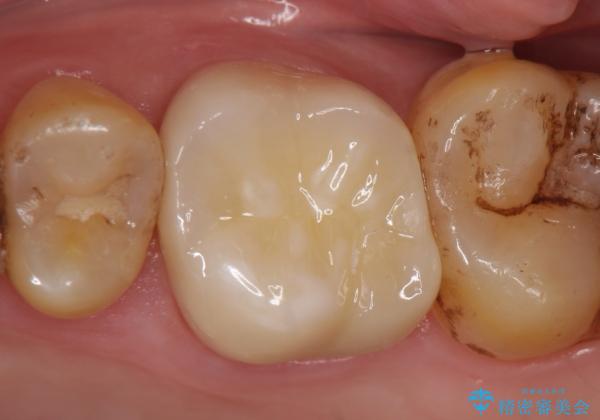

根尖病変の縮小及び症状の消失を確認後、オールセラミッククラウンによる補綴を行いました。

今回用いたオールセラミッククラウンはジルコニアフレームという白い素材の上にセラミックを盛っているため、審美性が非常に高いのが特徴です。

また、ジルコニアは人工ダイヤモンドの材料にも使われているほど高い強度を持っており、そのためオールセラミッククラウンは審美性だけでなく、奥歯やブリッジの補綴も可能とするクラウンです。